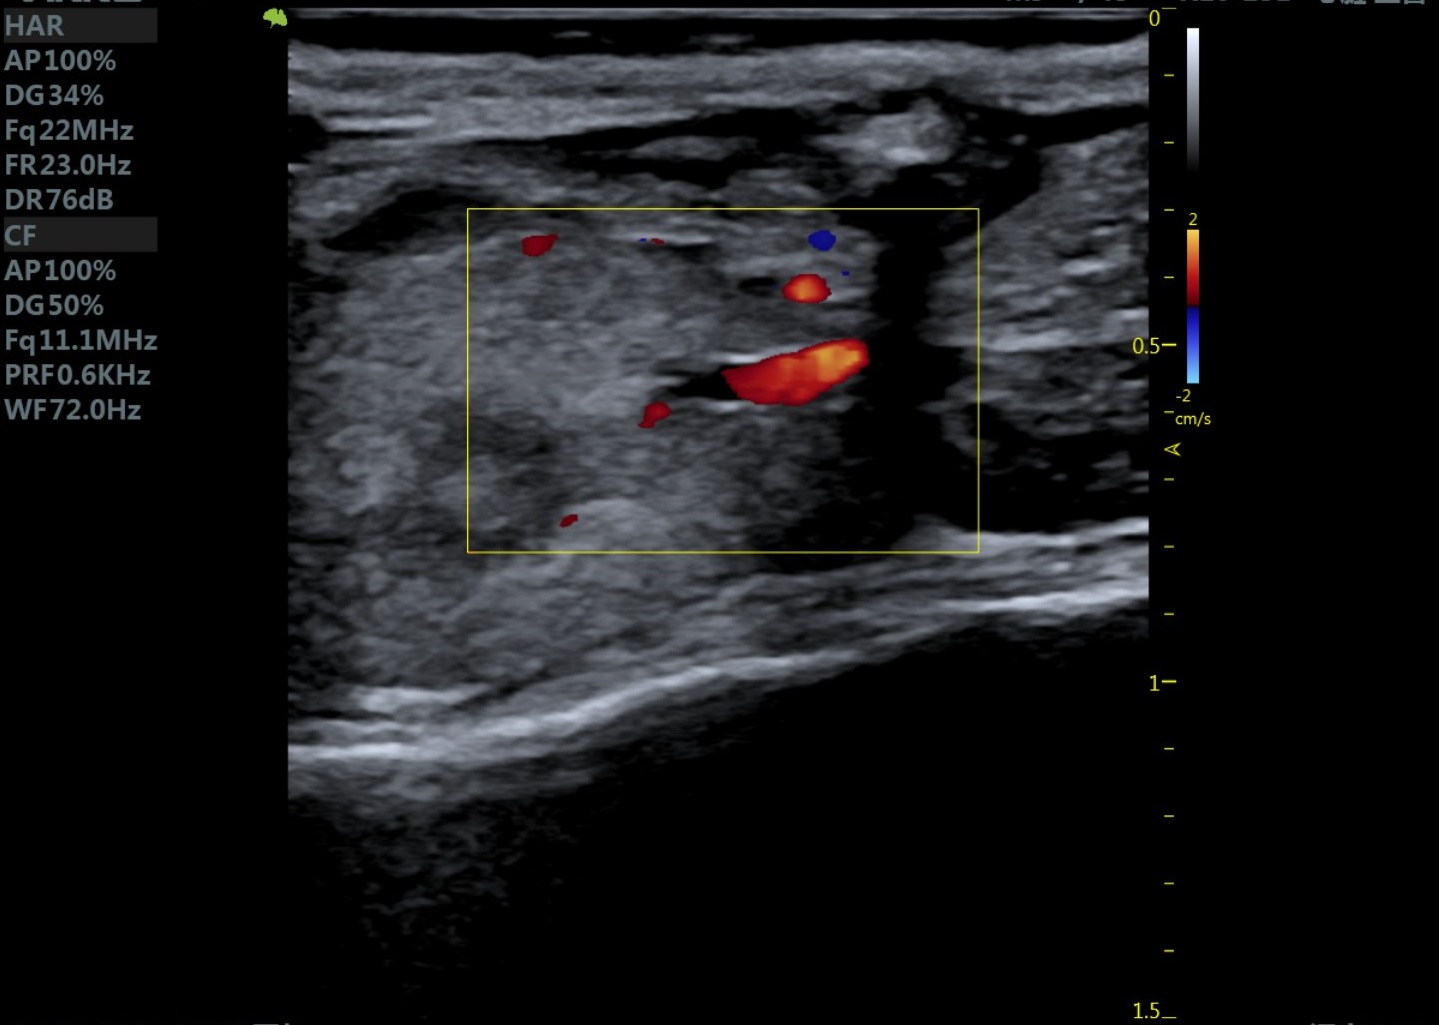

小鼠主动脉弓 小鼠肾脏血流